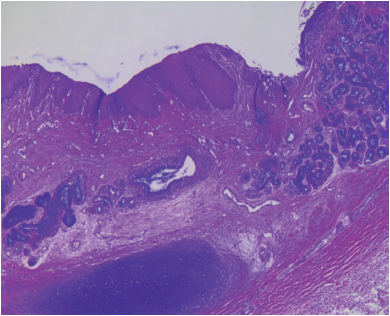

Los cortes histológicos de la tráquea mostraron epitelio ulcerado con depósitos de fibrina, tejido de granulación, inflamación aguda y crónica, con área extensa de metaplasia escamosa (Figura 4).

El pulmón mostró abundante moco en sus luces bronquiales y bronquiolares, los alveolos presentaban abundantes macrófagos en su luz entremezclados con polimorfonucleares, linfocitos y material eosinófilo denso (Figura 5A), así como engrosamiento moderado de la pared (Figura 5B).

El intersticio mostró fibrosis moderada a la tinción de Masson e infiltrado inflamatorio leve, compuesto por linfocitos (Figura 6A). Los vasos presentaron ligero engrosamiento de la pared y se identificó vaso arterial de mediano calibre con trombo intraluminal (Figura 6B).